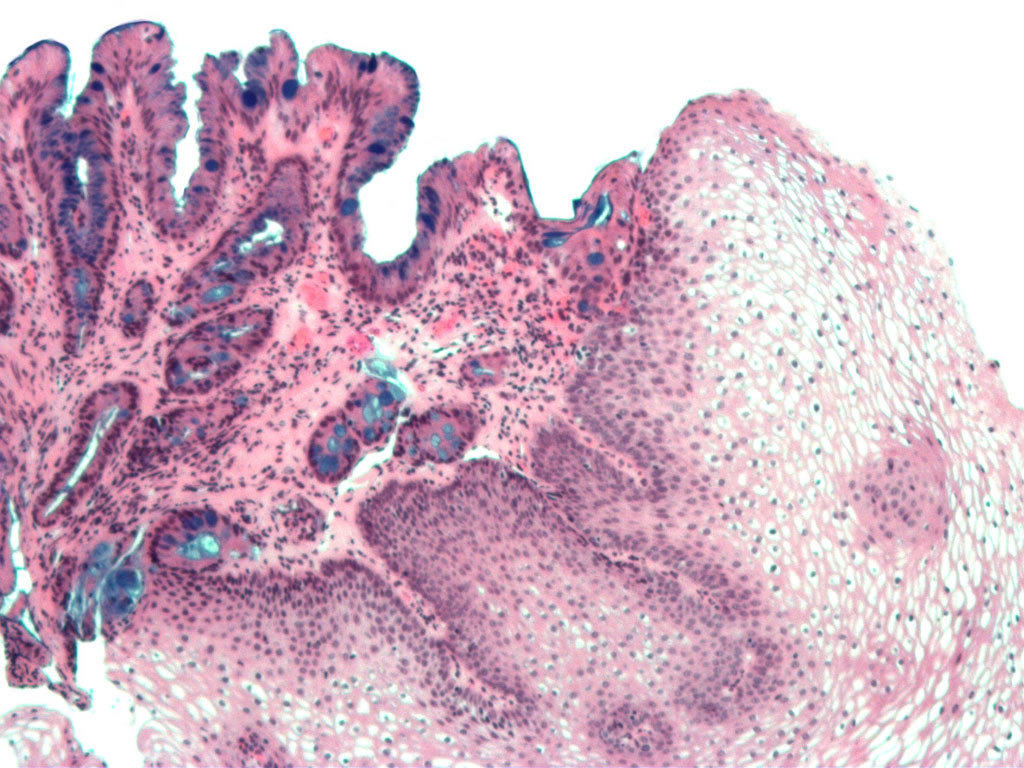

Bác sĩ thường chuẩn đoán bệnh thông qua nội soi thực quản bằng cách đặt một ống có gắn đèn vào miệng và đưa xuống thực quản. Sau đó, bác sĩ cũng có thể sử dụng phương pháp sinh thiết để kiểm tra các bất thường ở thực quản bằng cách lấy một mẫu mô nhỏ kiểm tra dưới kính hiển vi.